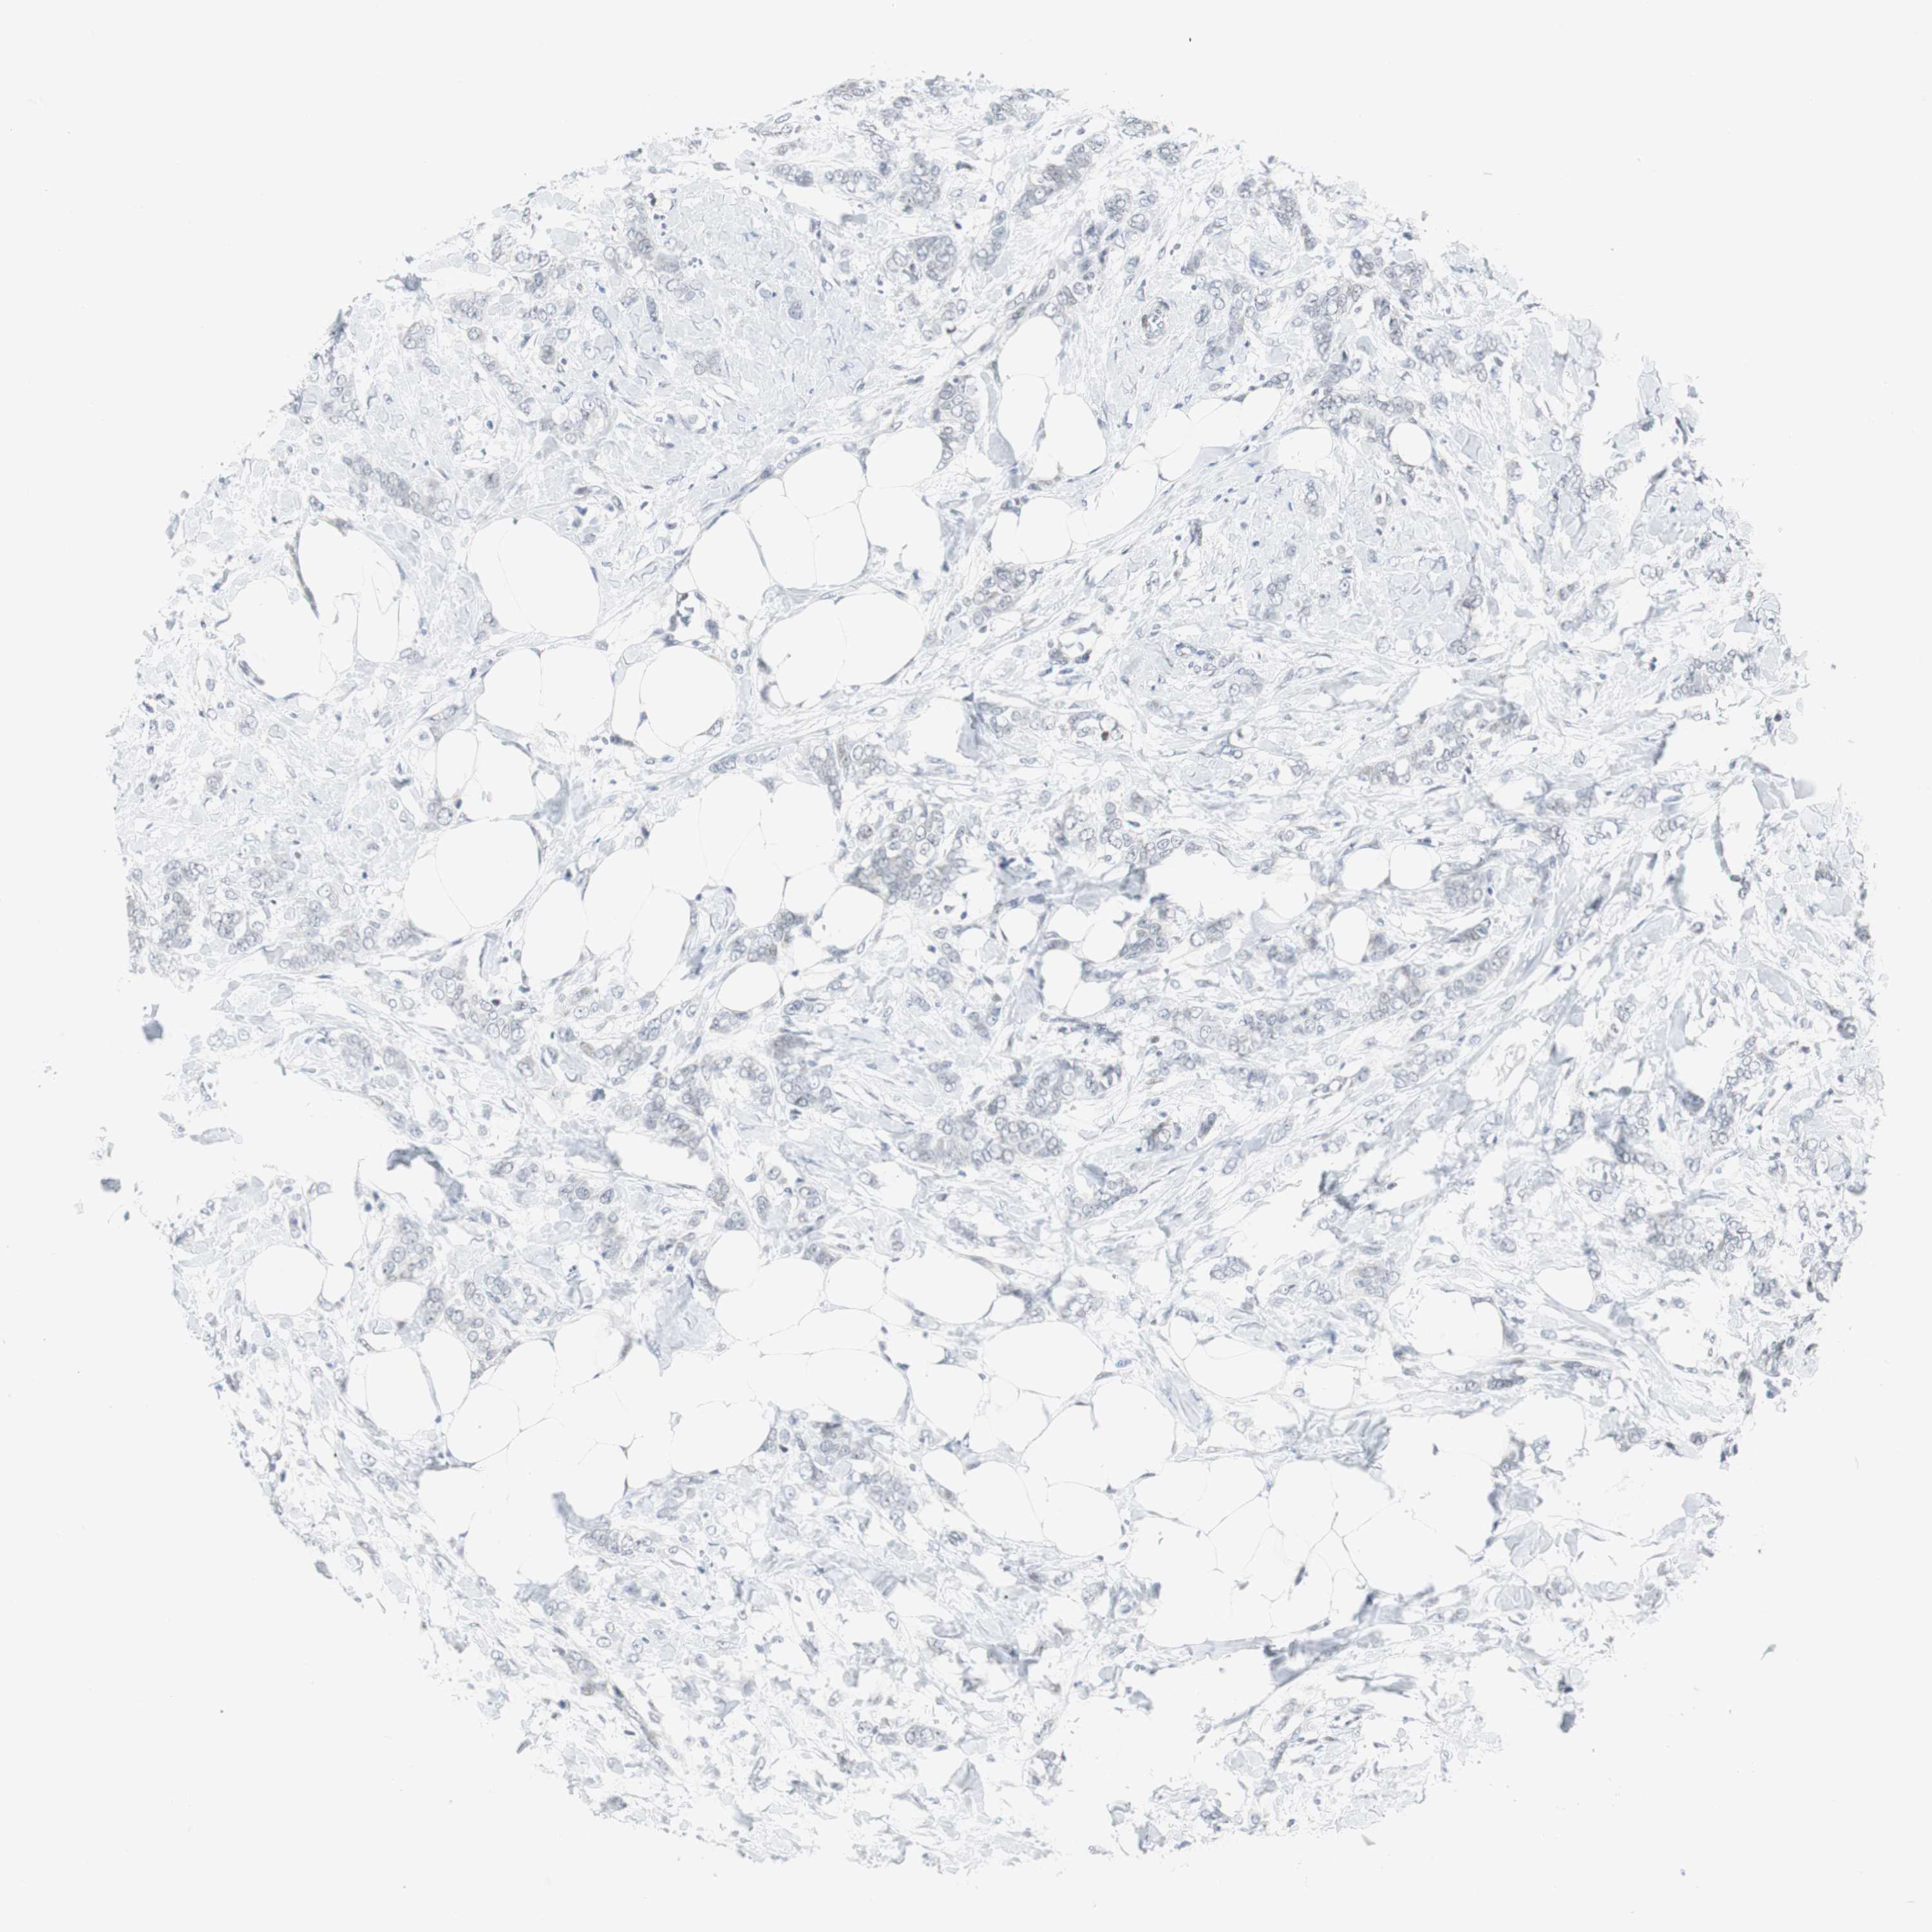

CANCER BREAST CANCER Show tissue menu

BRCA TCGA BRCA VALIDATION PROTEIN EXPRESSION